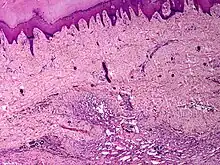

| Skin angiomatosis | |

Angiomatosis is a non-neoplastic condition[1] characterised by nests of proliferating capillaries arranged in a lobular pattern, displacing adjacent muscle and fat.[2] It consists of many angiomas.[3]

It is a vascular malformation wherein blood vessels proliferate along with accompanying mature fat and fibrous tissue, lymphatics and sometimes nerves.[2] They may involve skin, subcutaneous tissue, skeletal muscle and occasionally bone.[2]